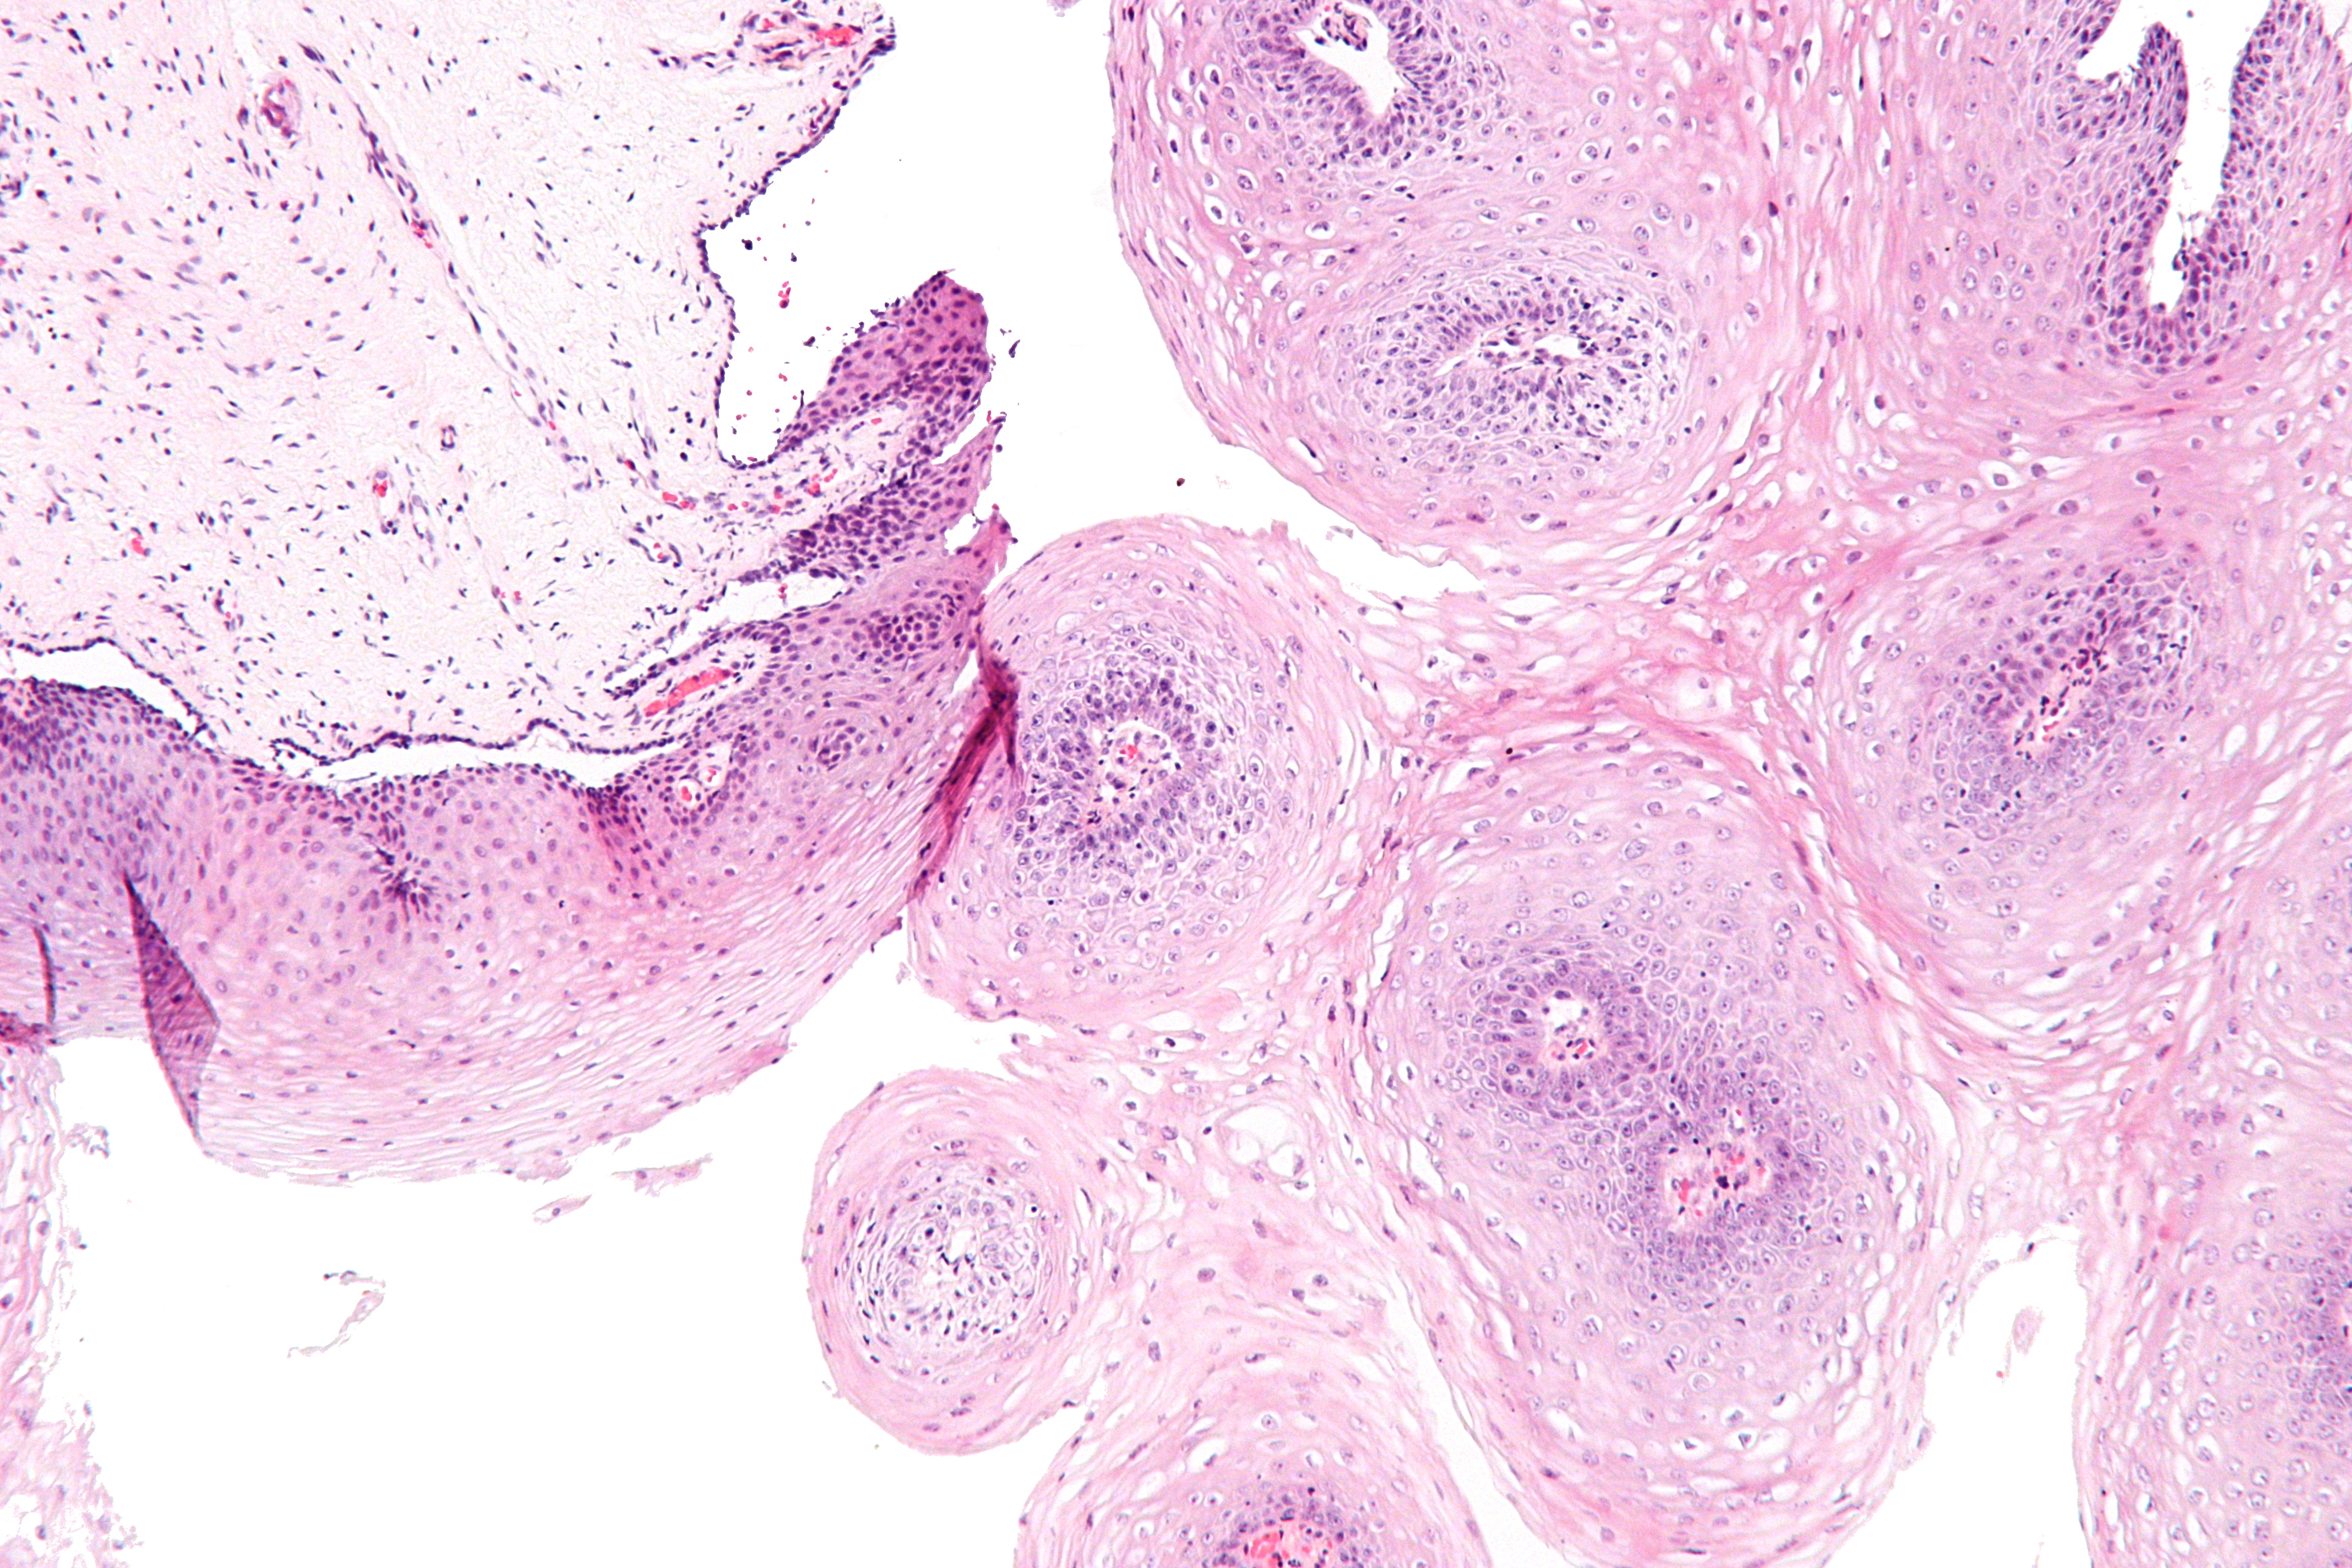

Симптомы кондилом могут варьироваться, и визуальное представление этого заболевания может быть различным. Некоторые кондиломы выглядят как небольшие бугорки или бородавки, в то время как другие могут иметь форму плоских пятен или цветных наростов.

Лечение кондилом требует профессионального медицинского вмешательства. Врач может рекомендовать различные методы лечения, включая применение лекарственных препаратов, криотерапию (замораживание бородавок) или хирургическое удаление.